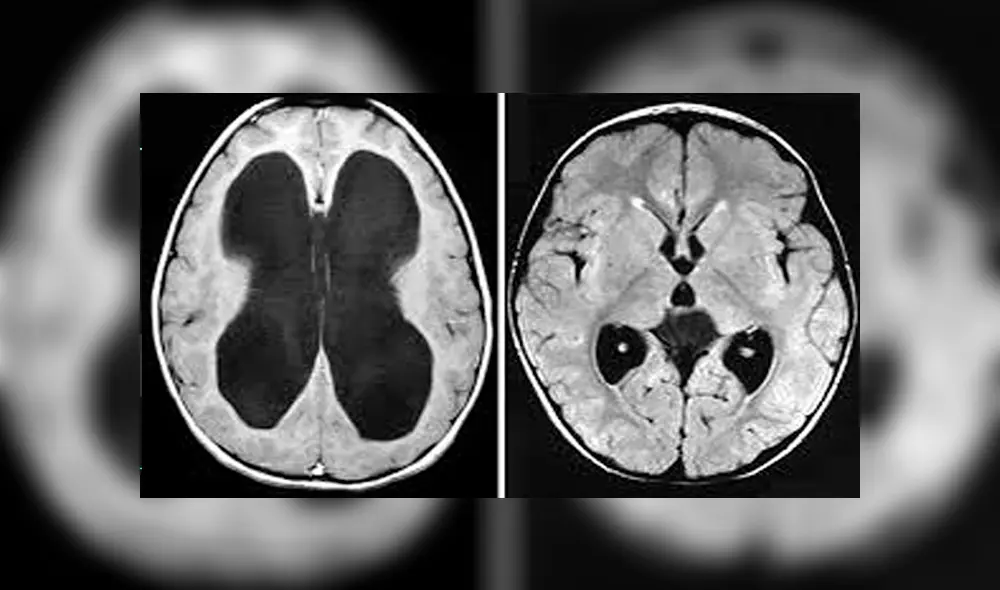

El síndrome de Hakim-Adams también es conocida como hidrocefalia de presión normal o hidrocefalia normotensiva y es causada por un aumento de líquido cefalorraquídeo en los ventrículos o cavidades del cerebro, lo que genera complicaciones a nivel neurológico.

Por esta razón, la hidrocefalia normotensiva puede llegar a pasar desapercibida al ser confundida con otras afecciones del sistema nervioso, como el Parkinson (por la alteración de la marcha) o el Alzheimer (por la disfunción cognitiva), lo que hace imposible el tratamiento y la recuperación del enfermo.

Otro de los indicios se da en el deterioro cognitivo progresivo, ya que se distorsiona el lóbulo central y las áreas subcorticales del cerebro.